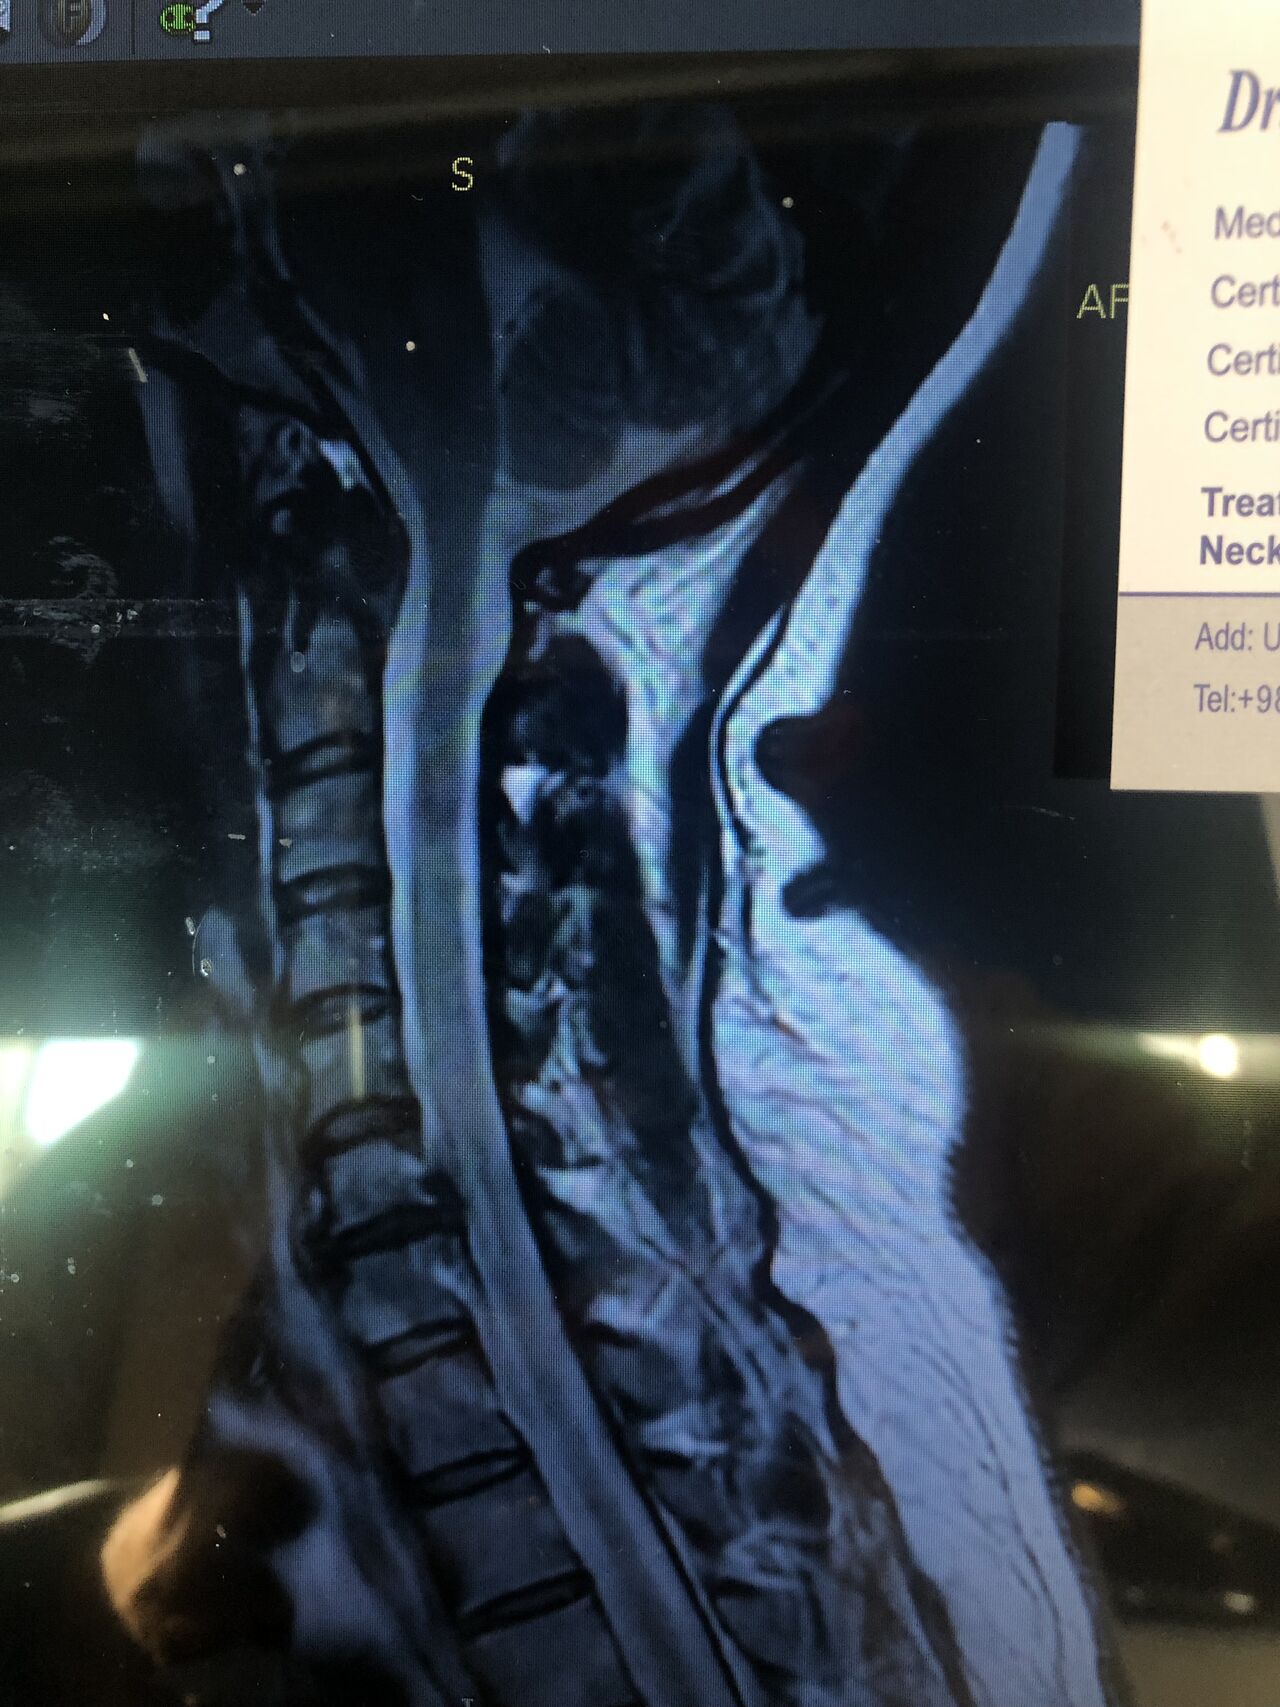

Case Report

A 56-year-old man presented with chronic low back pain and mild neck stiffness. Lumbar MRI confirmed disc degeneration. In cervical MRI C5-6 Cervical extrusion with cervical cord compression is seen

And neurological exams were normal for cervical spine

therefore according to the cervical mri no cervical treatment was rendered to his neck

Insurance initially denies paying for MRI but patients can pay themselves if they want to get neck adjustment

.cervical adjusting was not rendered and patient was referred to the neurosurgeon